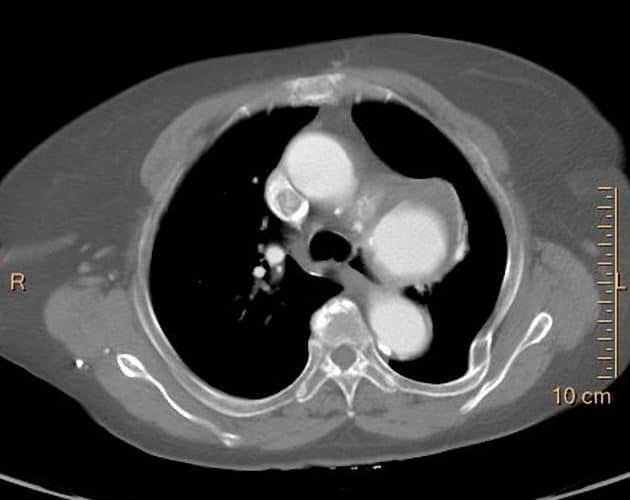

Phình ĐM chủ ngực - Ảnh 3

Phình ĐM chủ ngực

» Thông tin: Nam giới – 65 tuổi.

» Lâm sàng: Đau ngực.